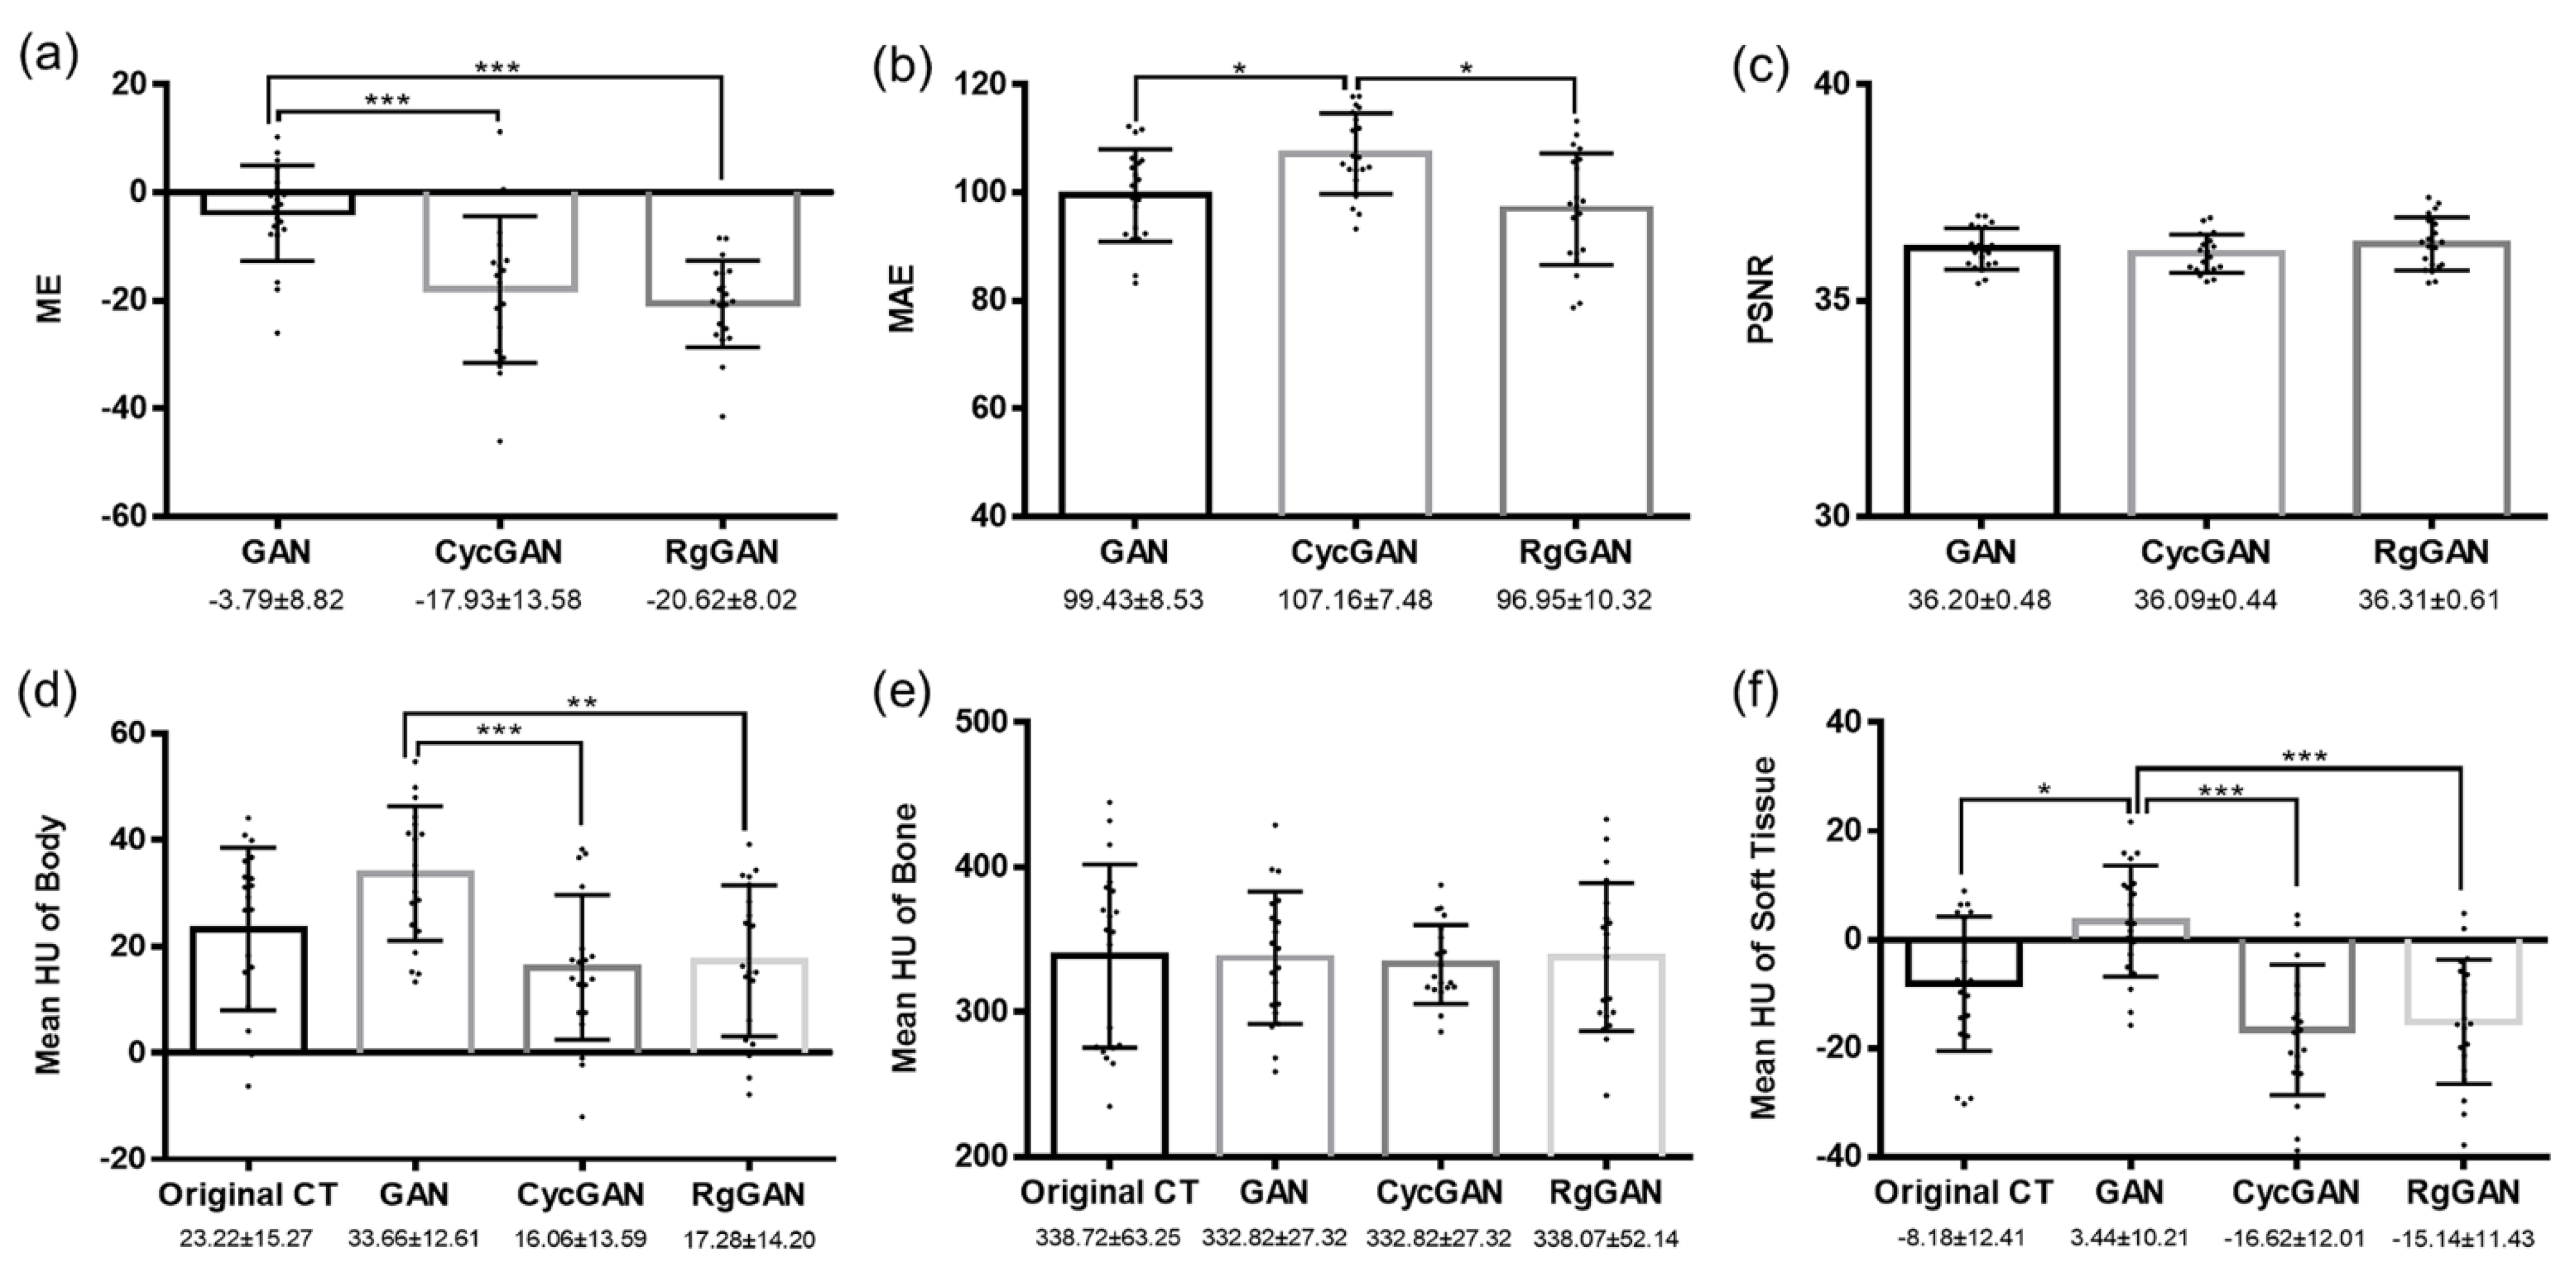

3.2. Image Quality

3.3. Dosimetric Comparison